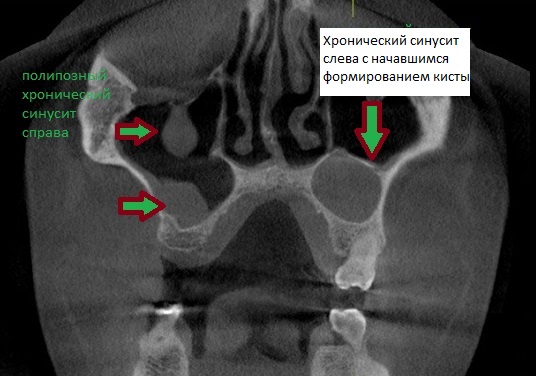

КТ-снимки хронического этмоидита: подробная визуализация